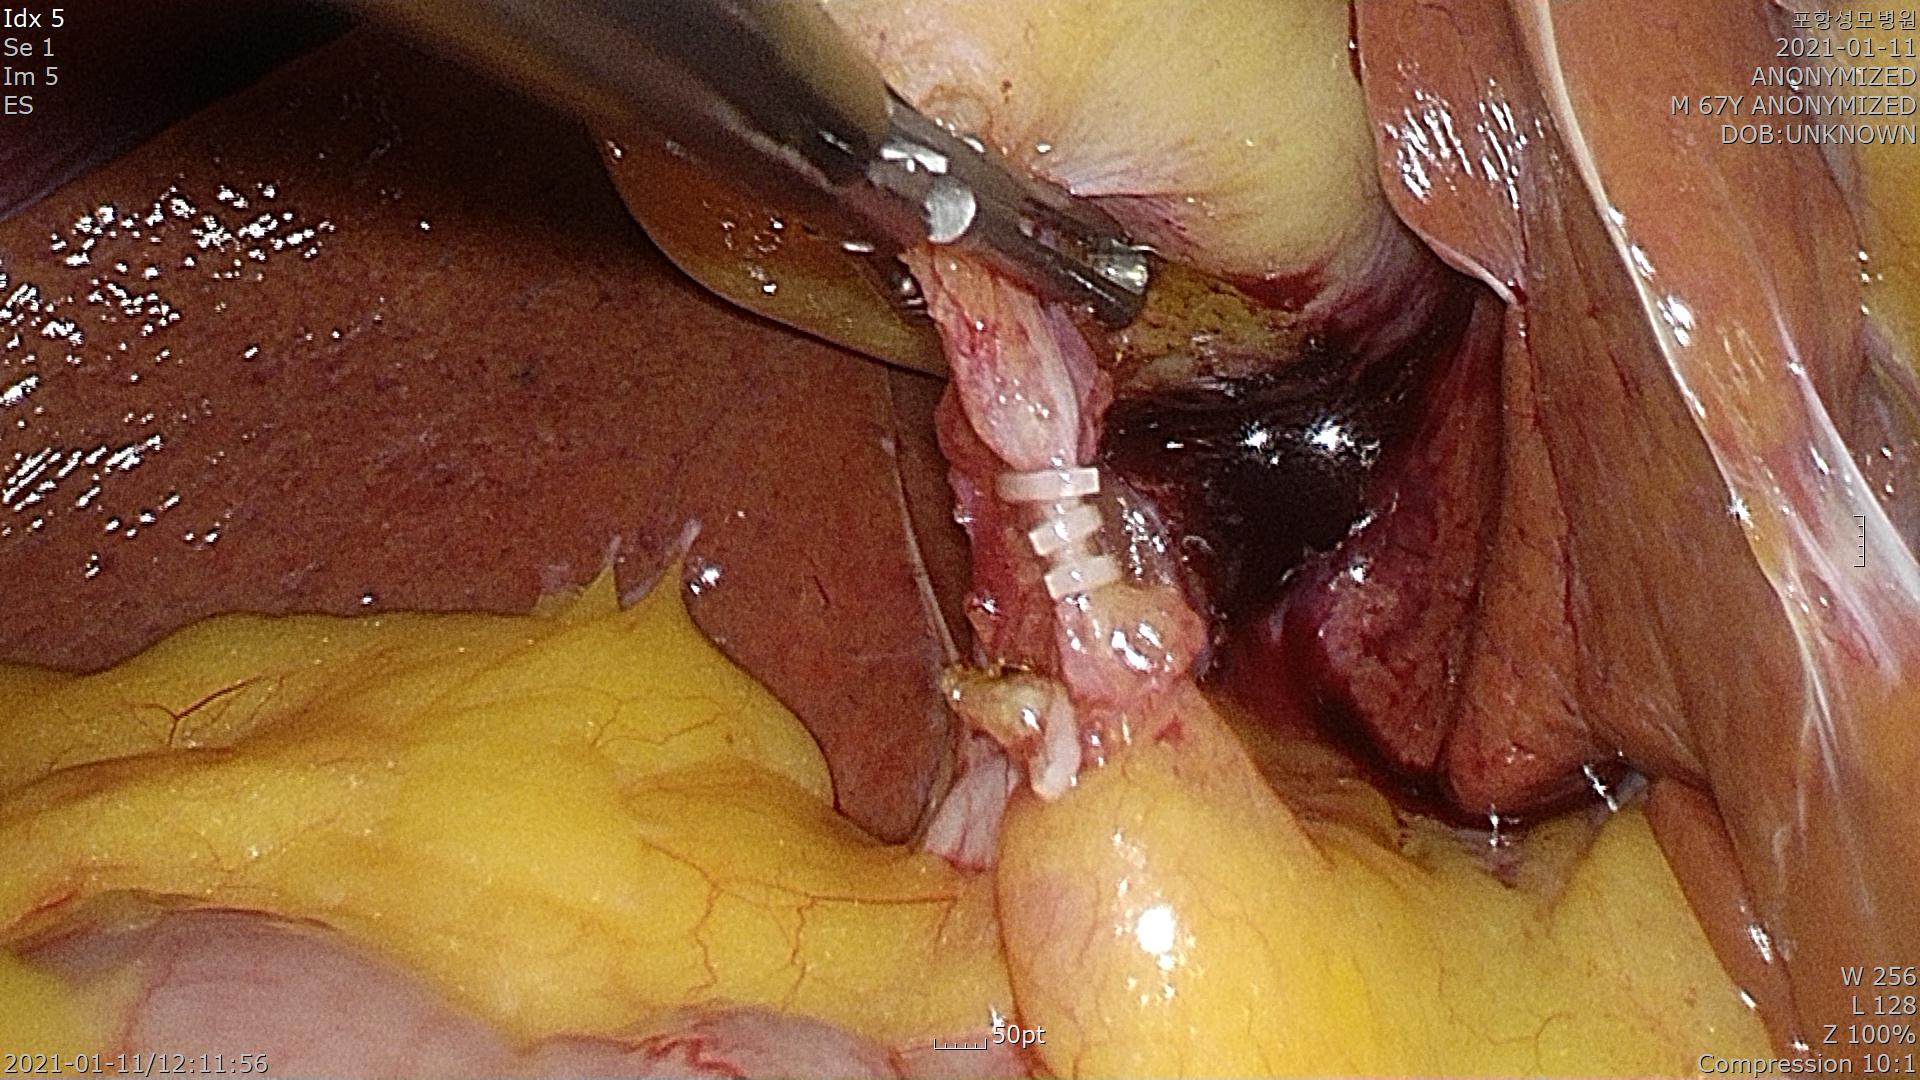

2021.1.11일 복강경 담낭절제술을 시행했습니다.

용종이 있을때 담낭 절제 수술은 담낭에 구멍을 내지 않고 간 후벽으로 부터 깨끗하게 절제해 내야 하는것이 수술의 핵심입니다.

정확한 조직학적 진단을 하려면 떼어낸 담낭이 간에 남지 않고 깨끗하게 제거되어야만 합니다.

혹시최종 조직검사에서 담낭암으로 진단되는 경우 암세포가 담낭벽을 얼마나 침범했나 여부에 따라 추가적인 수술을 해야하는 경우가 있기 때문입니다.

담낭을 확인합니다.

담낭관을 정확히 박리하여 결찰합니다.

간후벽에서 담낭을 분리해냅니다.

깨끗하게 담낭이 절제된 모양입니다.

담낭은 천공 없이 깔끔하게 제거되었습니다.

화살표를 기준으로 왼쪽이 간 후벽에 붙어 있던 담낭 부분입니다.

제 입으로 말씀드리기 부끄럽지만 스스로도 만족스러운 수술 이었습니다.

수술 시간은 30분 걸렸습니다.